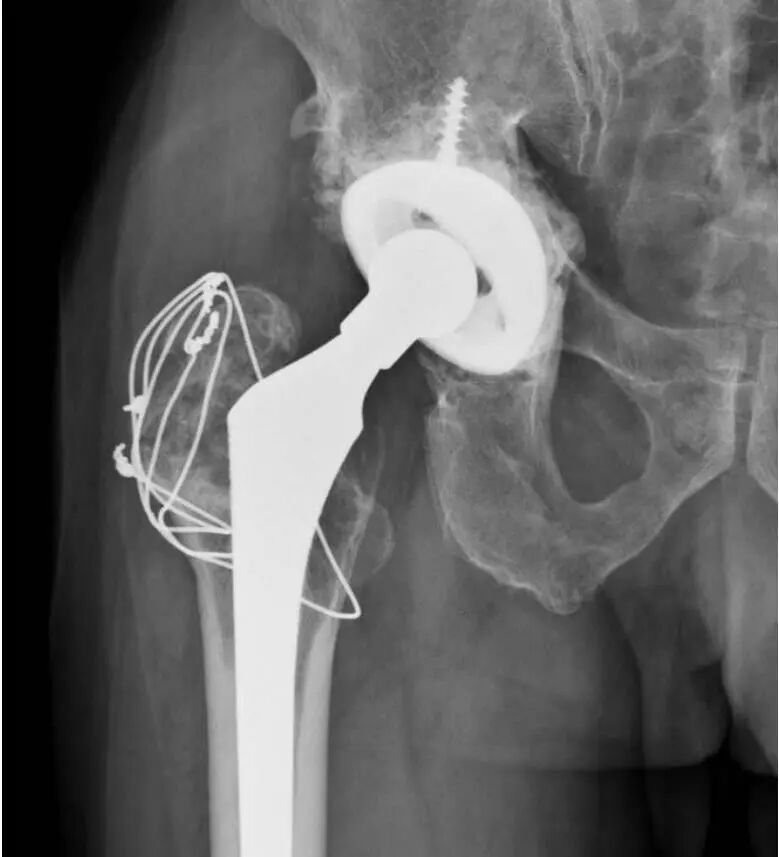

图5:A和B,一名57岁女性的左髋部X光片。A:无骨水泥全髋关节置换术后7年的正位X线片显示,由于聚乙烯磨损,股骨头关节偏心,大转子移位骨折并伴有溶骨性病变(箭头)。B:X线片,髋臼假体翻修8年后,用双张力带钢丝固定大粗隆并植入同种异体骨,显示大粗隆良好愈合和同种异体骨融合。

图6:A和B,一位69岁男性假体周围骨盆骨溶解,无骨水泥全髋关节置换术后12年的大转子和小粗隆的右髋位X线片。A:翻修手术前的x光片。B组:髋臼假体翻修一年后行大转子切开复位内固定,2根张力带钢丝和1根斜环扎钢丝,辅以异体骨移植,显示大转子骨折愈合。